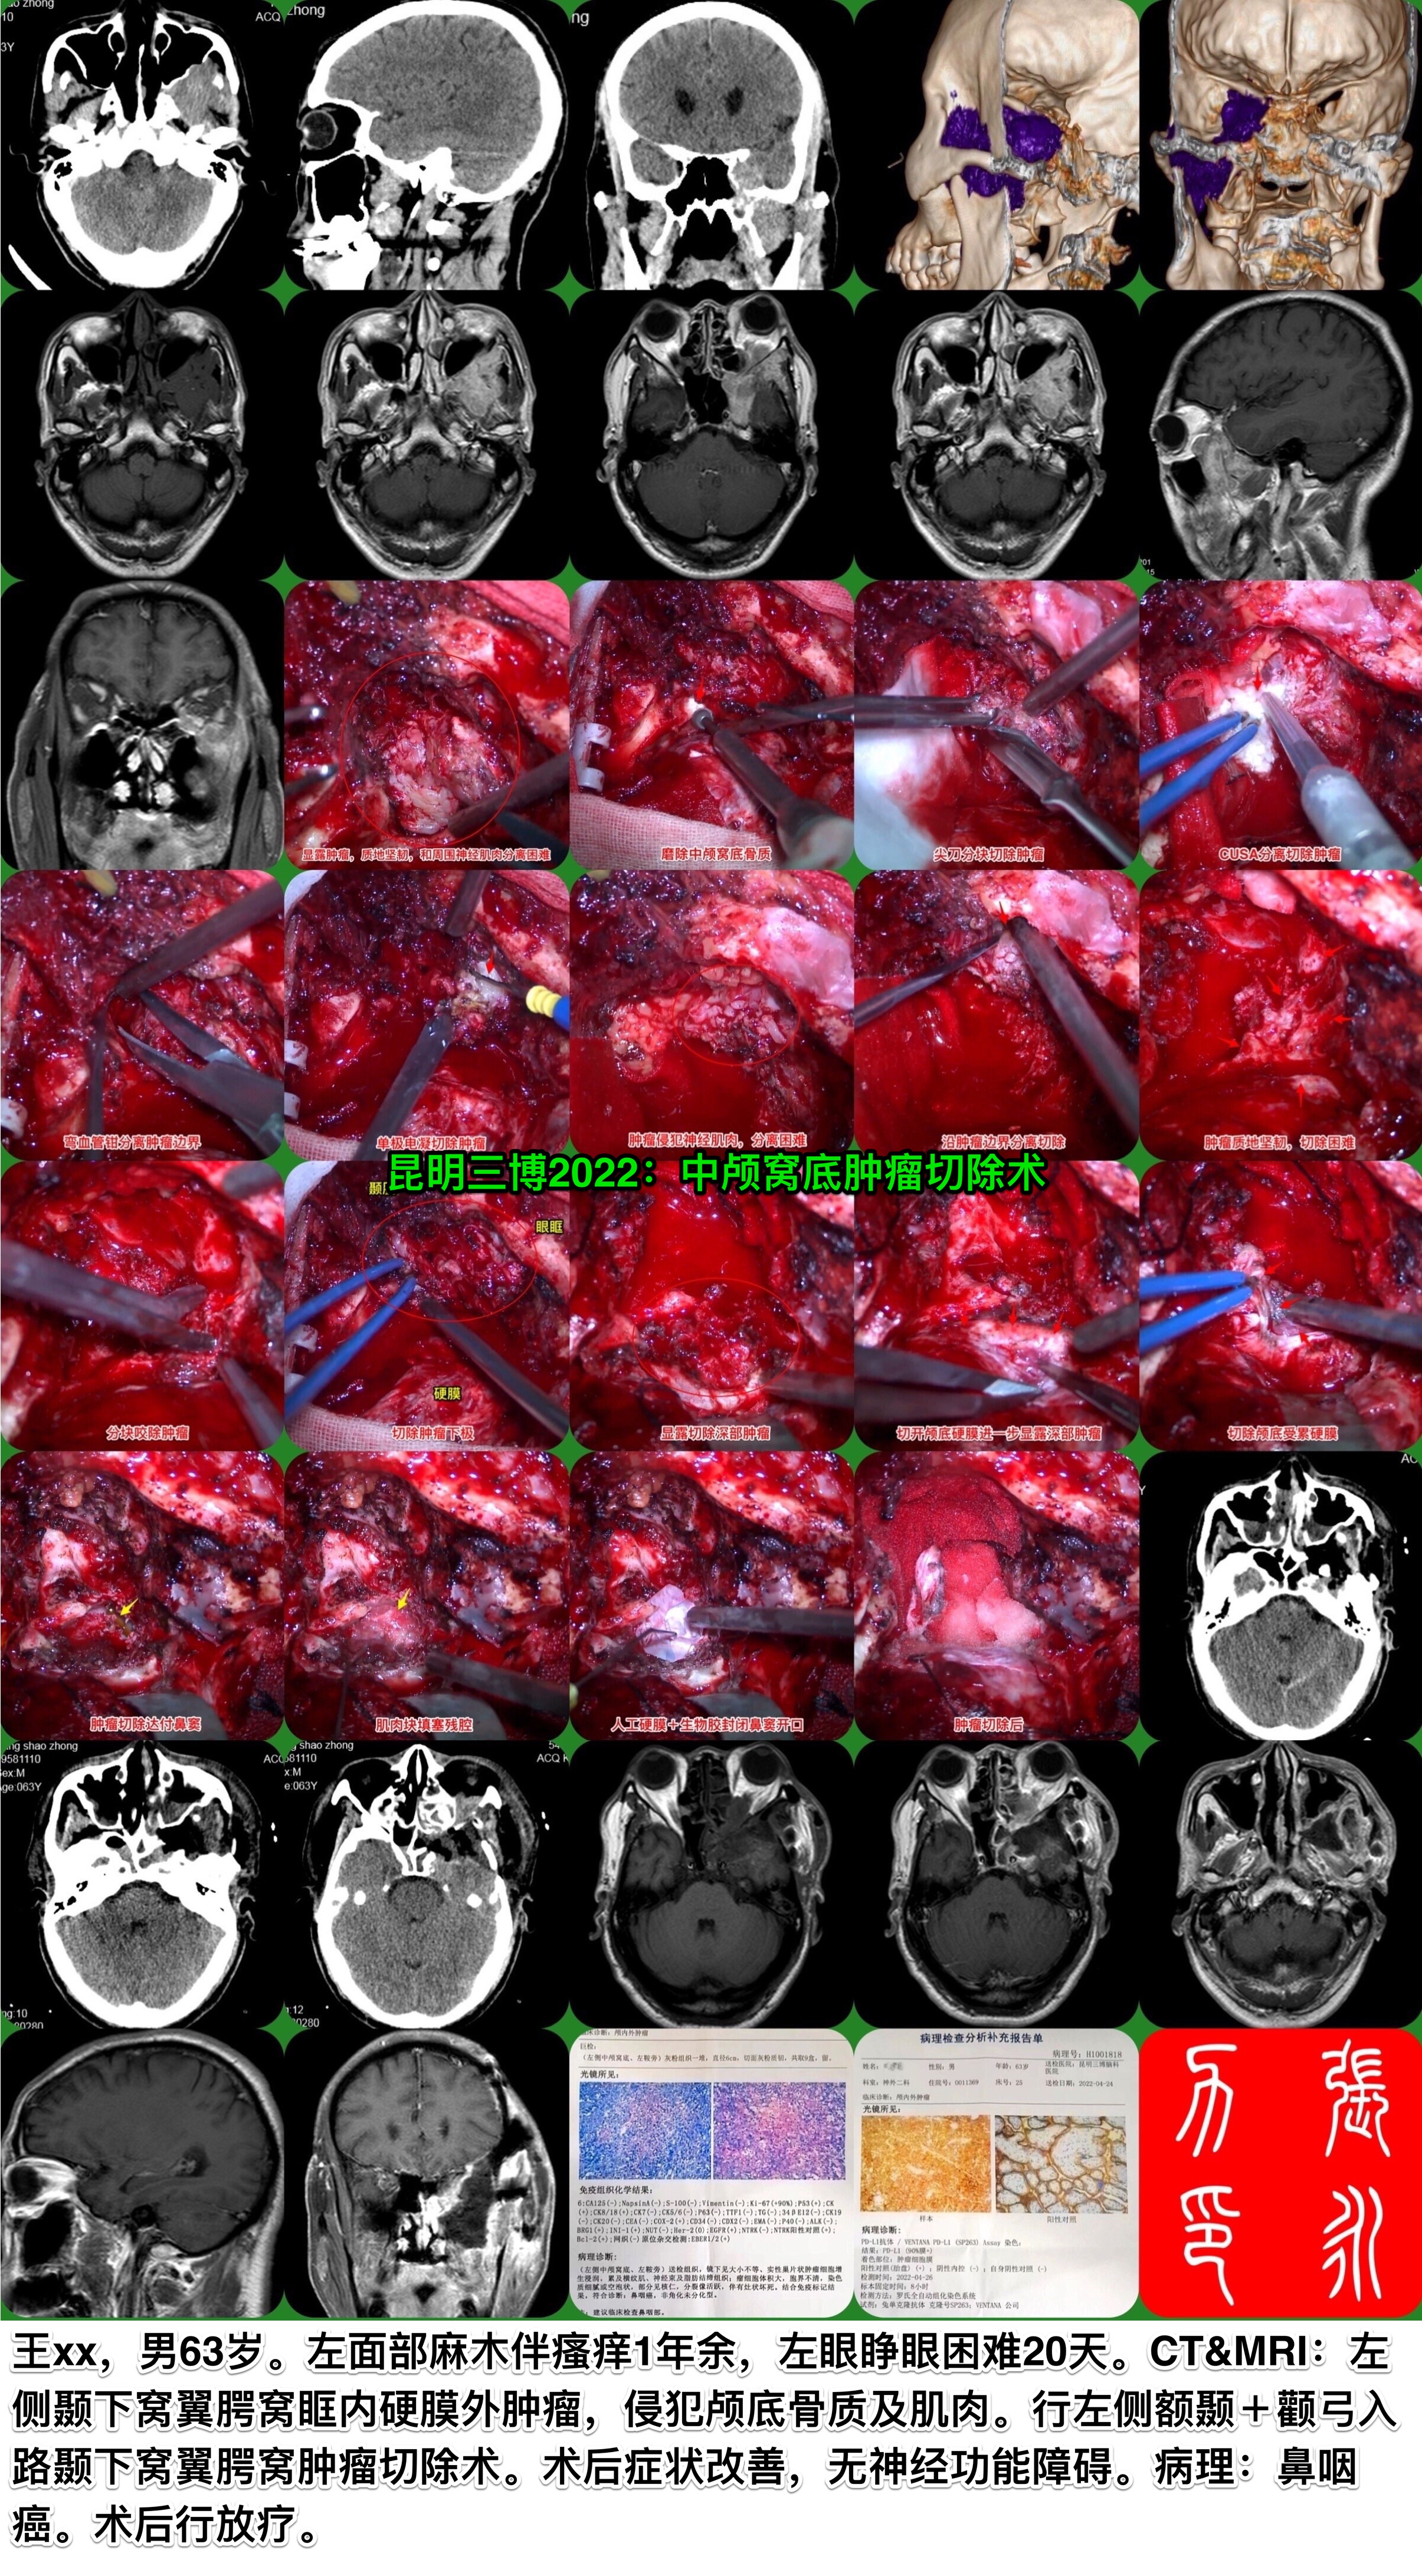

昆明三博2022:中颅窝底肿瘤切除术